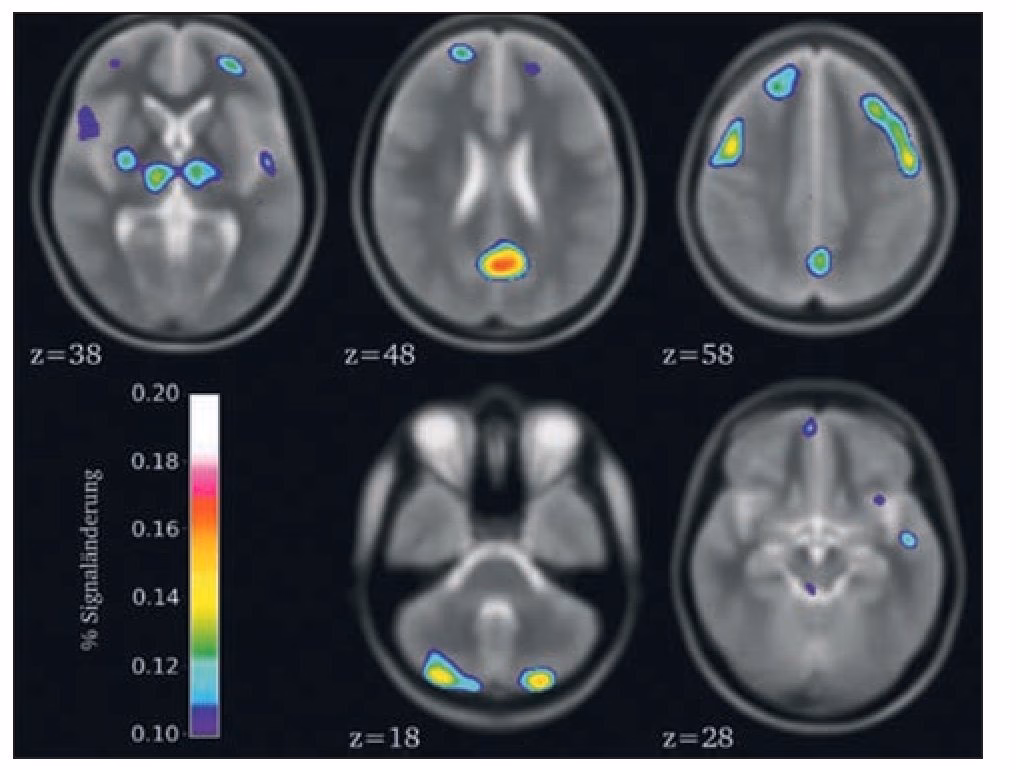

Dado que hablamos de la posibilidad de que un acupunturista ordene una RMN, es útil entender qué es y cómo se realiza este procedimiento. Una Resonancia Magnética es una técnica de imagen médica que utiliza un campo magnético potente y ondas de radio para crear imágenes detalladas de los órganos y tejidos del cuerpo. Es particularmente útil para visualizar tejidos blandos, como el cerebro, la médula espinal, los nervios, los músculos, los ligamentos y los órganos internos.